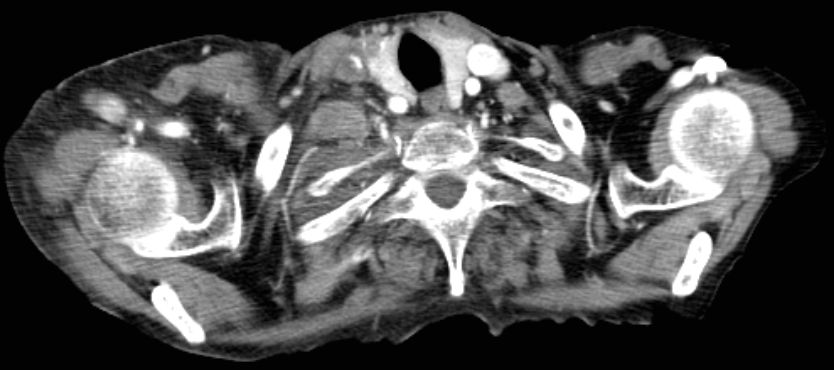

| Supraclavikuläre Lymphknotenmetastase | Lymphknotenmetastase unter der medialen Clavikula

links. ![]() |